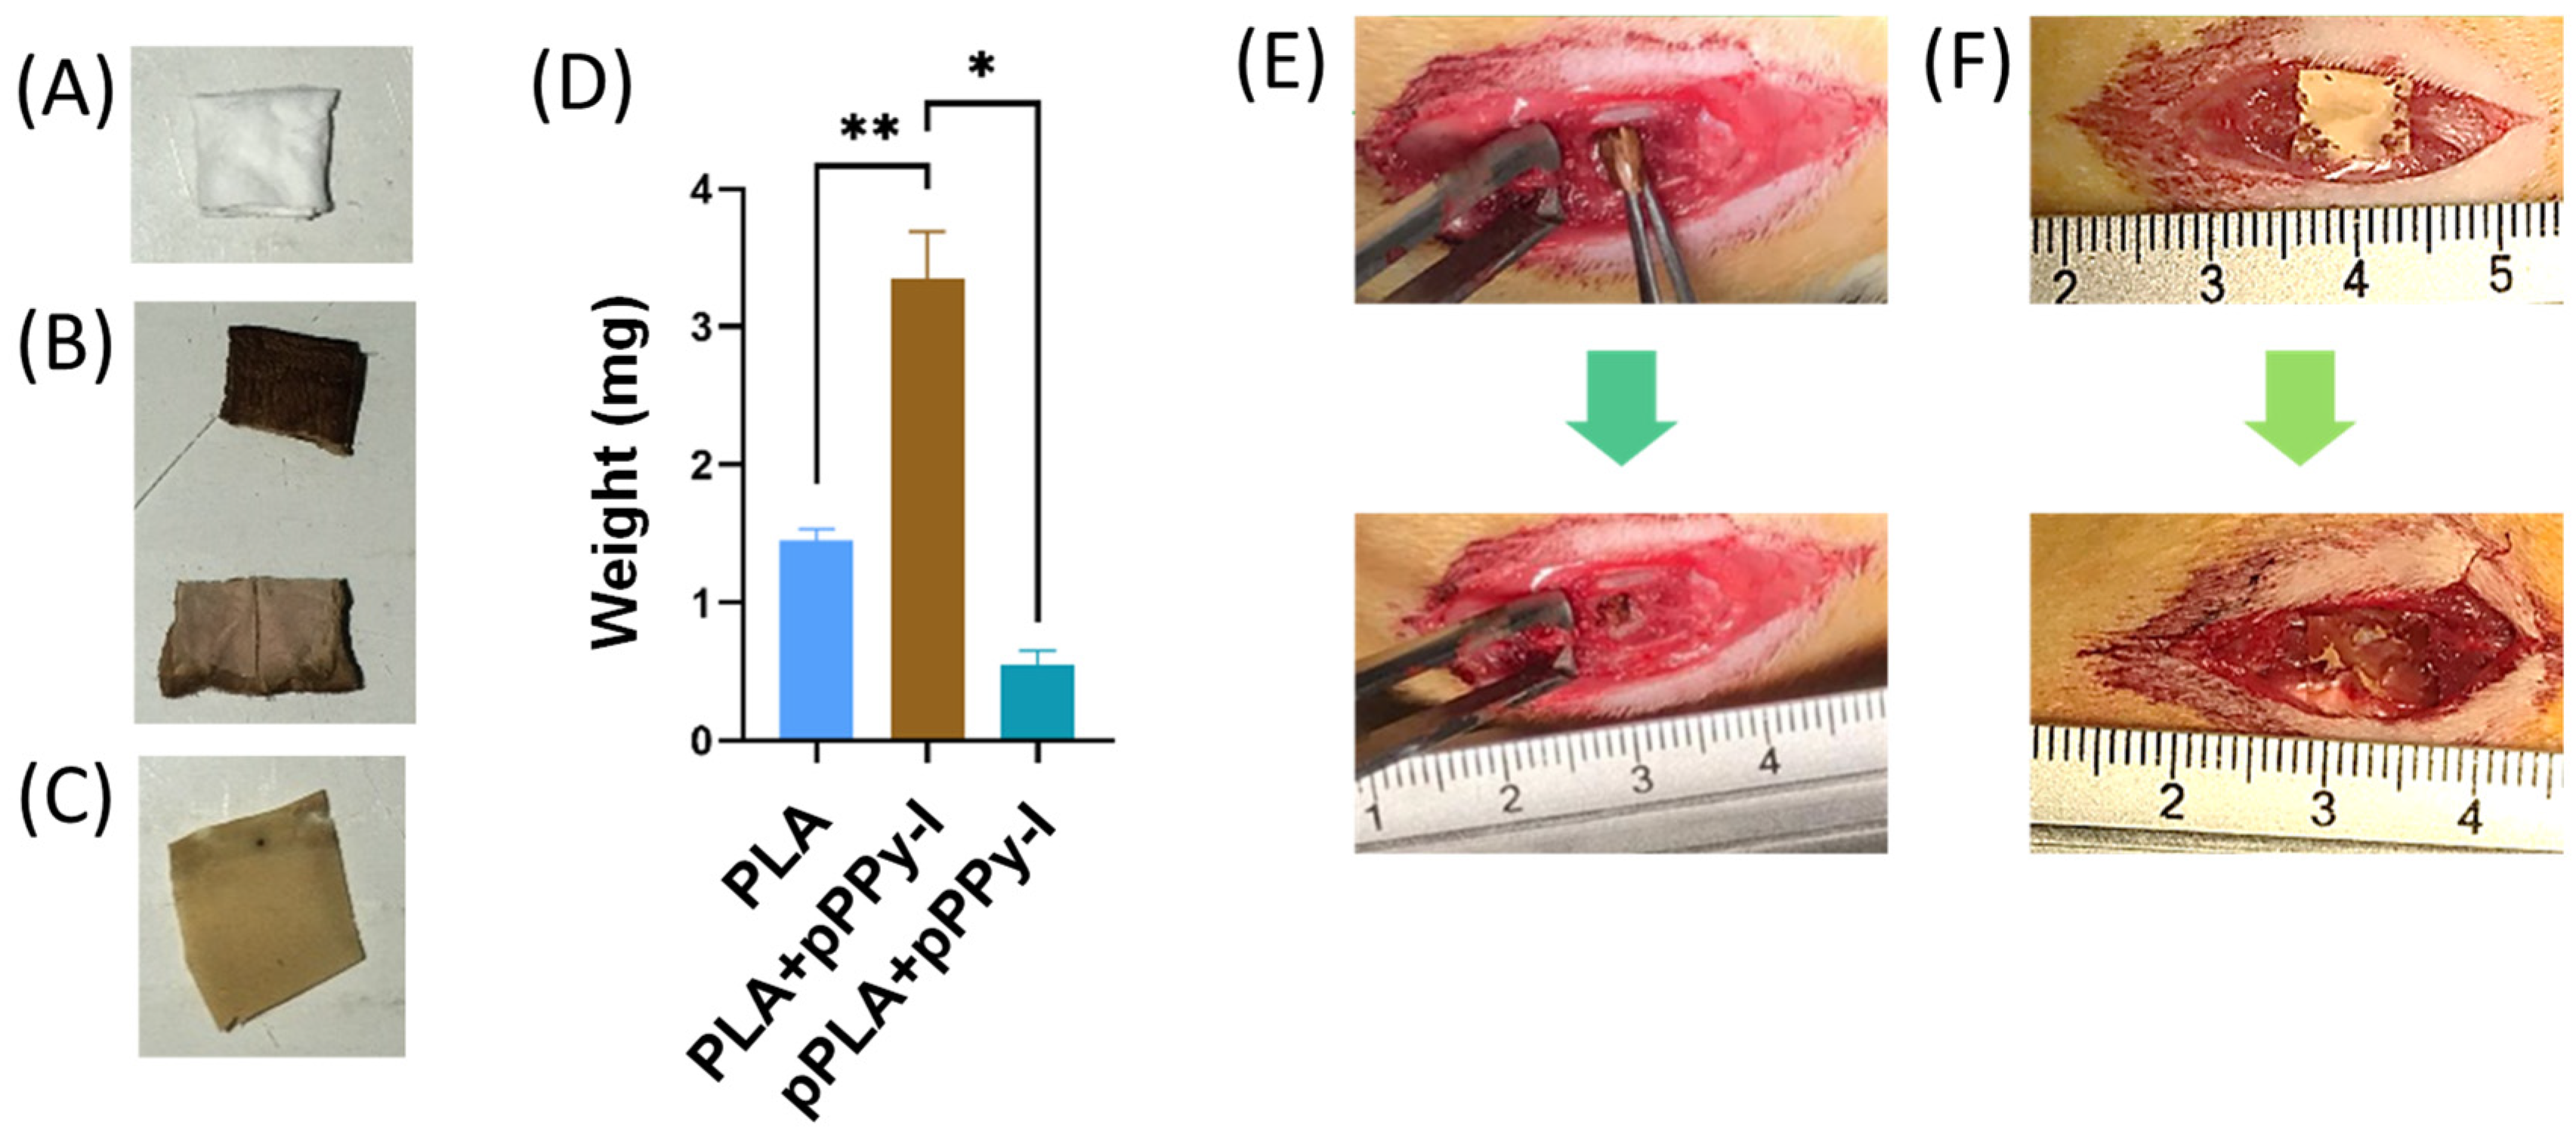

3.1. Scaffold Design and Rapid Tissue Response to Plasma-Modified Scaffolds